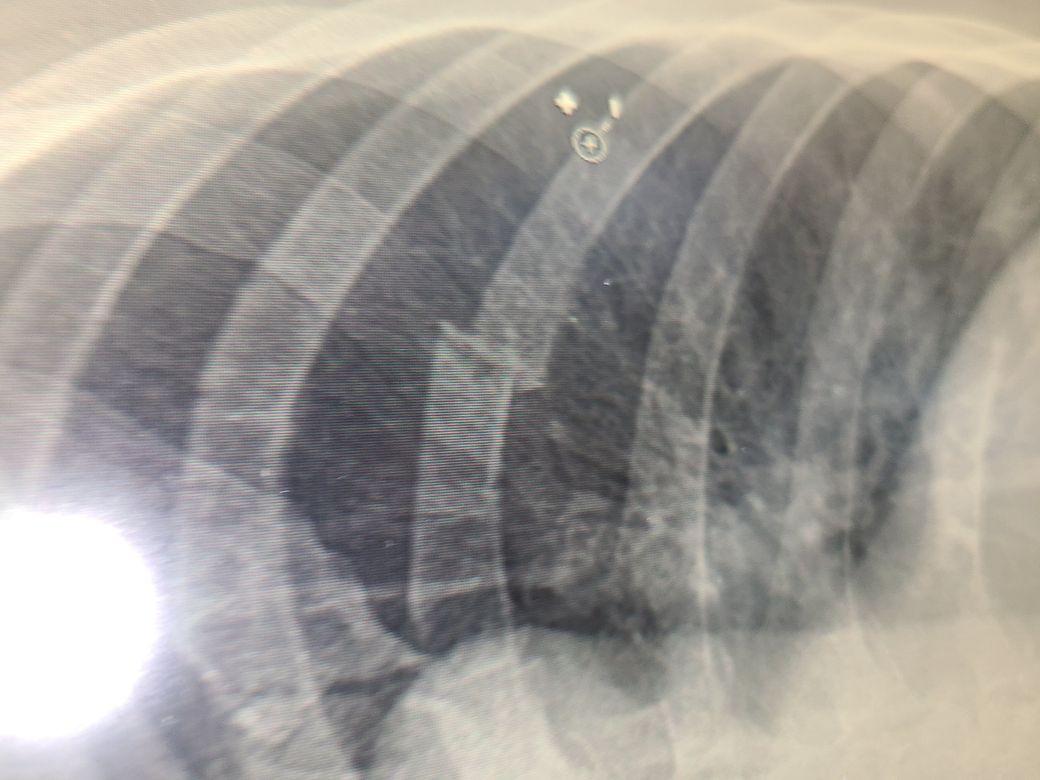

골프를 두달정도 배웠는데 왼쪽6번늑골이 골절되었습니다. 기침한번 할때마다 너무 고통스럽습니다. 현재 병원에서 처방해준 약만 먹고 있는데 자연치유기간이 얼마나 되나요? 골프는 당분간 하면 안되겠죠?

많이 아프실 듯 합니다. 일반적으로 늑골 골절은 4주 정도의 회복 기간을 가져야 합니다. 당연히 골프와 같이 상체를 많이 사용하는 운동은 피해야 합니다. 많이 움직일 수록 회복은 더뎌집니다.

갈비뼈 골절은 골프에서 쉽게 동반됩니다. 뼈를 다른뼈처럼 고정할수 없고 호흡시마다 움직이기 때문에 회복에 시간이 오래 걸리고 개인마다 편차가 큽니다 최소 한달이상 소요될 것으로 사료됩니다. 골프는 불가능합니다.

일반적으로 뼈가 잘 붙는 어린이의 경우 2주, 성인은 4주 정도의 시간이 소요됩니다. 자연치유가 잘 이루어지는 편입니다.